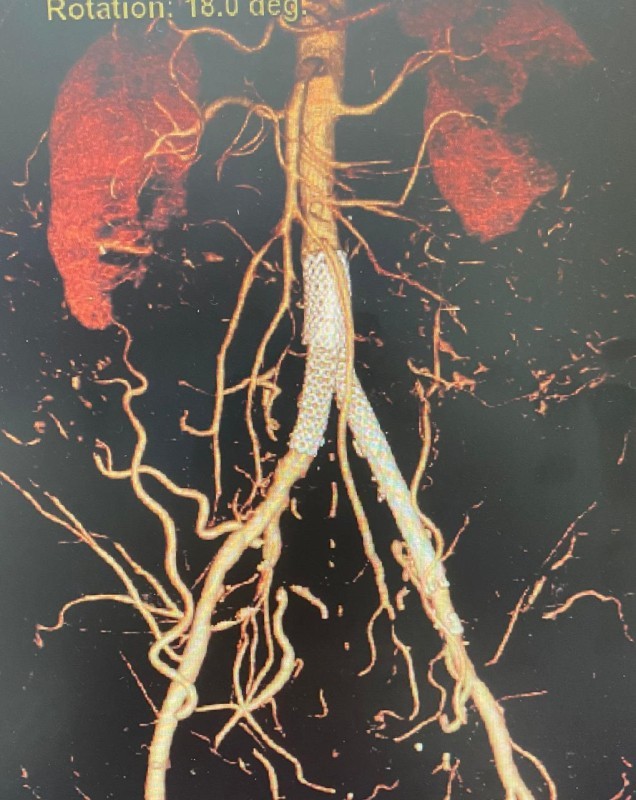

وقام الفريق الطبي بالعملية من خلال الدخول بالقسطرة عن طريق شريان الذراع وشرايين الفخذ، بعد ذلك تم فتح الشريان الأورطي بحرص شديد دون أي تأثير على شرايين الكلى أو الأمعاء، وبحمد الله تمت توسعة الشريان ووضع دعامات في الشرايين دون الحاجة للجراحة المفتوحة.

توصف العملية بالفريدة من نوعها، إذ إنها تجنب المريض مخاطر الجراحة المفتوحة والحاجة لفتح البطن والفخذين، مع وجوب تنويم المريض لفترة طويلة، ناهيك عن مضاعفات الجراحة المفتوحة في هذه الحالات على القلب والتهابات وآلام شديدة بعد العملية.

ويذكر أن تقنية فتح الشريان الأورطي وشرايين الحوض بالقسطرة تعتبر حديثة على مستوى العالم، وبدأ التوسع فيها منذ عام 2013، وتحتاج لمهارة عالية ولتوفر جميع الإمكانات في المستشفى حتى تكون الجاهزية على أعلى مستوى في حال - لا سمح الله - احتاج المريض للتحويل للجراحة المفتوحة.